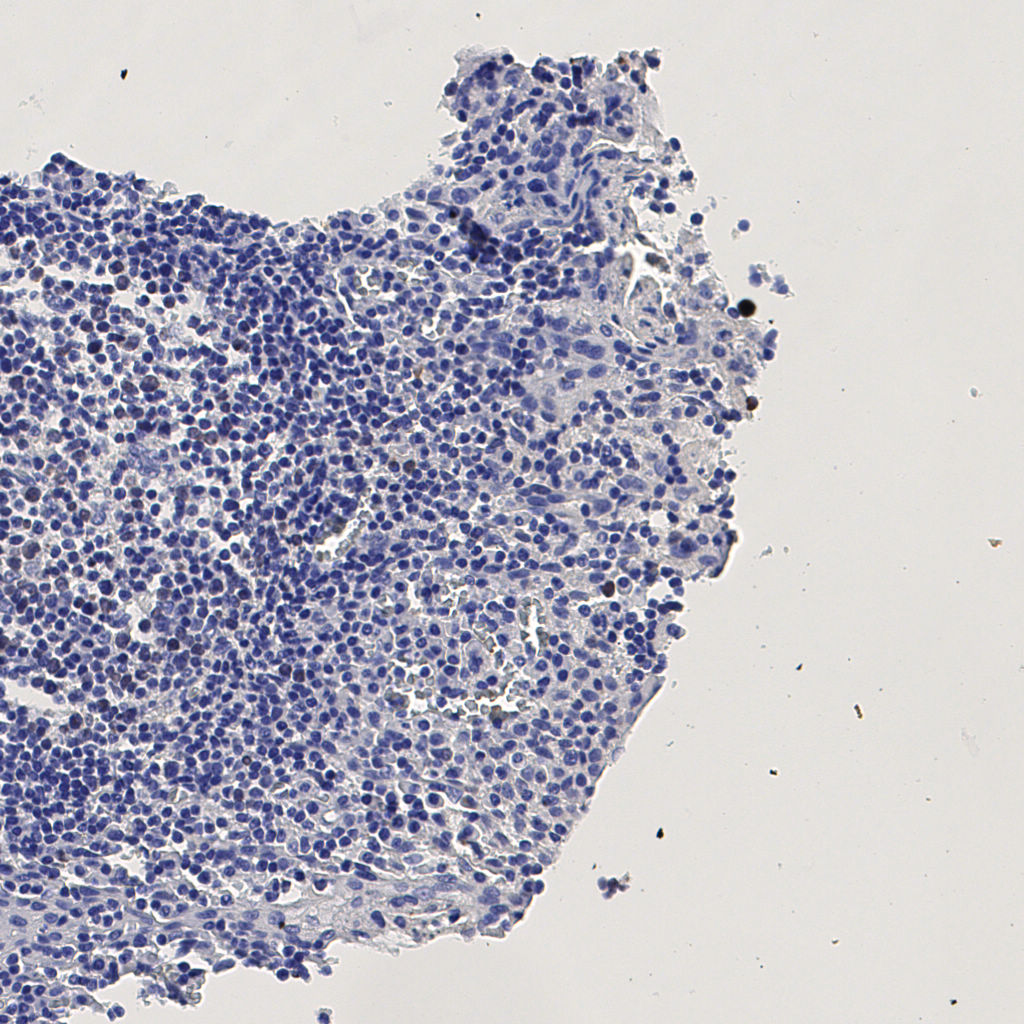

7.85%

Ki67 指数

阴 1104 阳 94